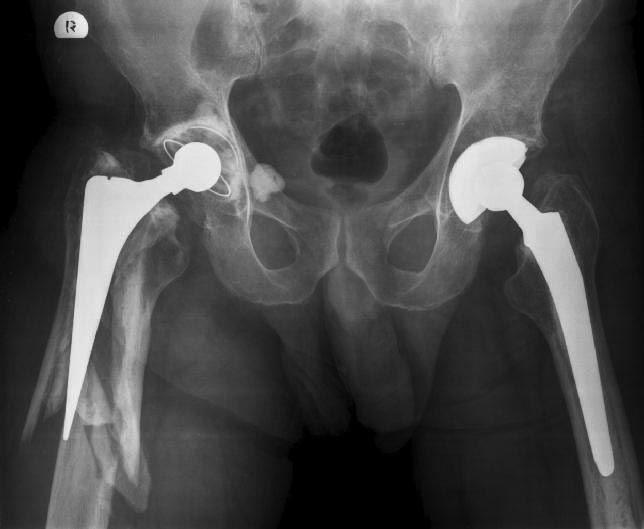

Перипротезный перелом

Снимки.